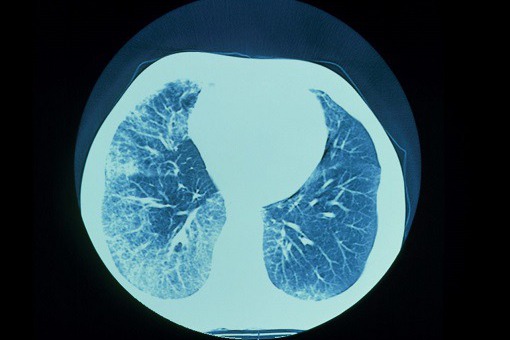

Zastosowanie analizy wydychanego oddechu za pomocą technologii eNose może pomóc w dokładnym rozróżnieniu podtypów śródmiąższowej choroby płuc (ILD) i może odróżnić pacjentów z ILD od osób zdrowych. Naukowcy przeprowadzili przekrojowe badanie w ośrodku Erasmus Medical Center w Rotterdamie w Holandii, a wyniki opublikowano w European Respiratory Journal.

Czujniki eNose rozróżniały pacjentów z ILD od zdrowych osób z grupy kontrolnej, z obszarem pod krzywą (AUC) wynoszącym 1,0 w zestawach treningowych i walidacyjnych. Kiedy porównano pacjentów z IPF z pacjentami z innymi ILD, analiza wykazała AUC 0,91 (95% CI, 0,85-0,96) w zestawie treningowym i AUC 0,87 (95% CI, 0,77-0,96) w zestawie walidacyjnym. Ponadto, dzięki zastosowaniu technologii eNose, można było wiarygodnie rozróżnić poszczególne podtypy ILD, z odnotowanymi wartościami AUC w zakresie od 0,85 do 0,99.

Głównym ograniczeniem obecnego badania jest fakt, że zdrowe osoby z grupy kontrolnej były znacznie młodsze i niepalące w porównaniu z osobami z różnymi podtypami ILD. Niemniej jednak badacze doszli do wniosku, że analiza wydychanego powietrza z wykorzystaniem technologii eNose może okazać się nowym biomarkerem u pacjentów z ILD, ułatwiając w ten sposób szybkie rozpoznanie choroby w przyszłości.